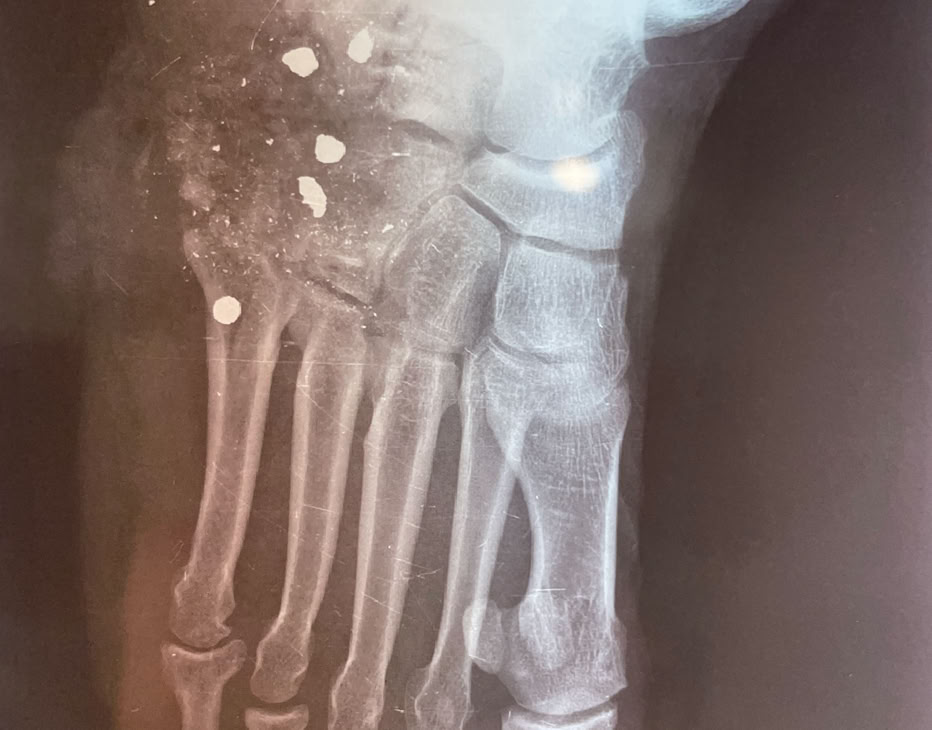

Nada más llegar, pase de visita para ver como empezar a programar las intervenciones de la semana. No había muchos pacientes ingresados pendientes de cirugía, pero no tuvimos que esperar mucho rato para recibir una herida por arma de fuego en un pie y una fractura de cadera de un paciente trasladado de un hospital de los Hermanos de San Juan De Dios que tratan enfermos de Lepra.

Ambos se resolvieron el lunes por la mañana con una prótesis parcial de cadera y el disparo en el pie con una cirugía de desbridamiento, limpieza y cierre.